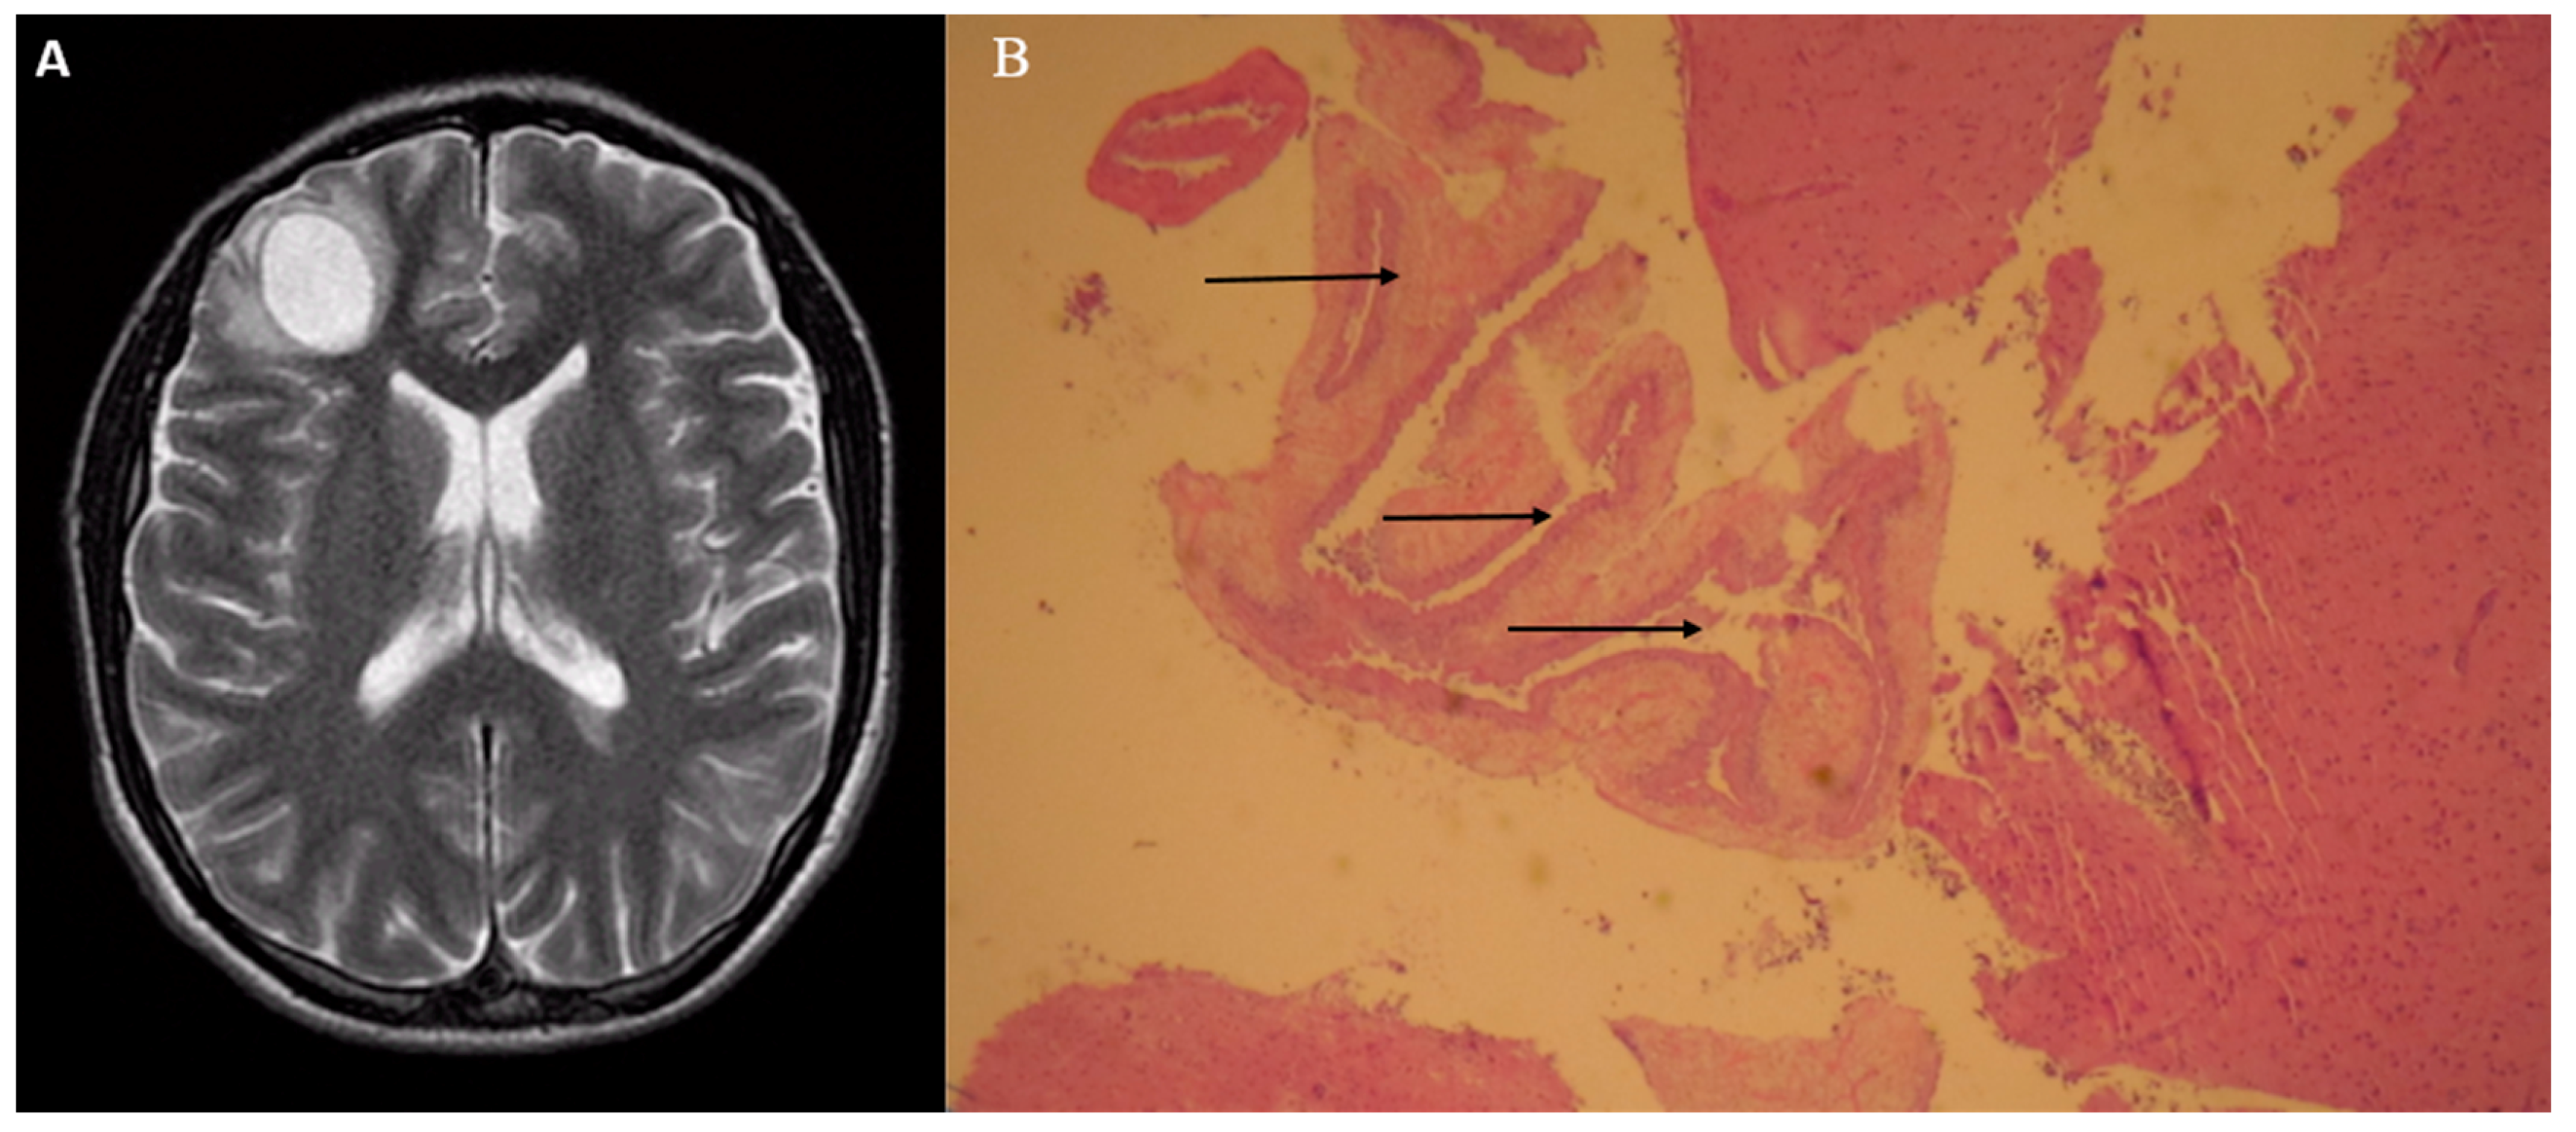

Solitary Brain Mass in a Patient with Seizures: An Unexpected Infectious Etiology